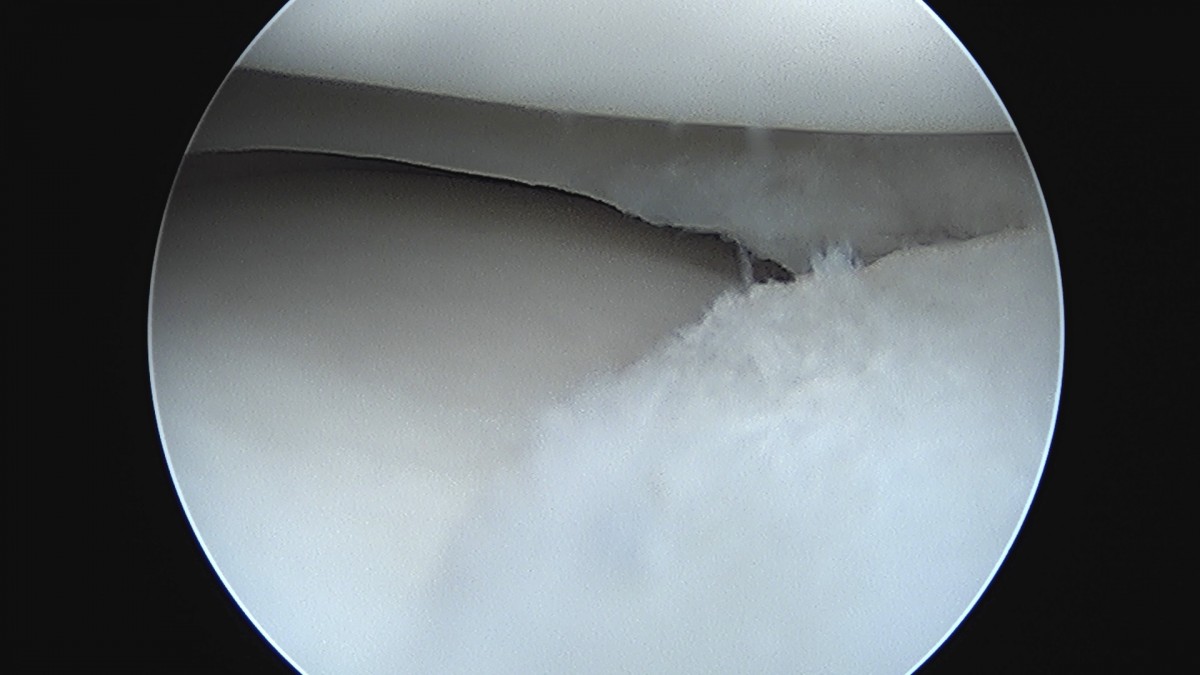

이재상원장님 무릎 반월상 연골판 절제술 김건O 환자

dae765e4d9ac96aee867c9d6292d8784_1758006495_2691.jpg